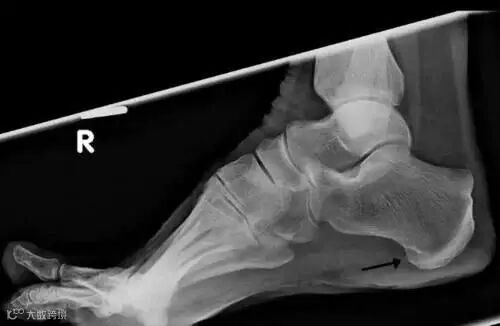

脚出现跖筋膜炎,没有及时治疗或持续慢性损伤,跟骨就可能出现“骨刺”(跖筋膜跟骨附着处的钙化)。